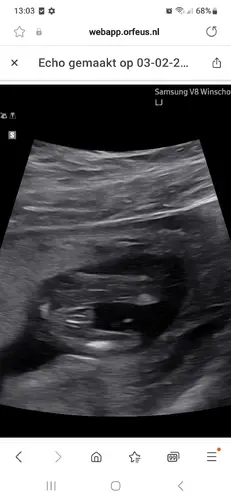

Iemand een idee? Verloskundige was 80% zeker.🙈

Meisje 🩷

Meisje!